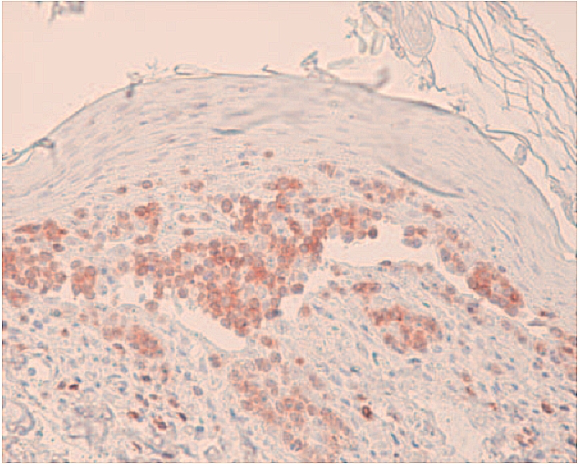

(2009)利用免疫组织学检测优化肿瘤诊断 免疫组织学(=免疫组织化学,IHC)可用于确定石蜡包埋、福尔马林固定的组织样本中的特定表位(抗原),可应用于组织学无法确诊的肿瘤病例,或是提供更特异性的细节(例如,恶性程度);可用于检测特定的感染原。 肿瘤诊断 2023年01月17日 15 浏览